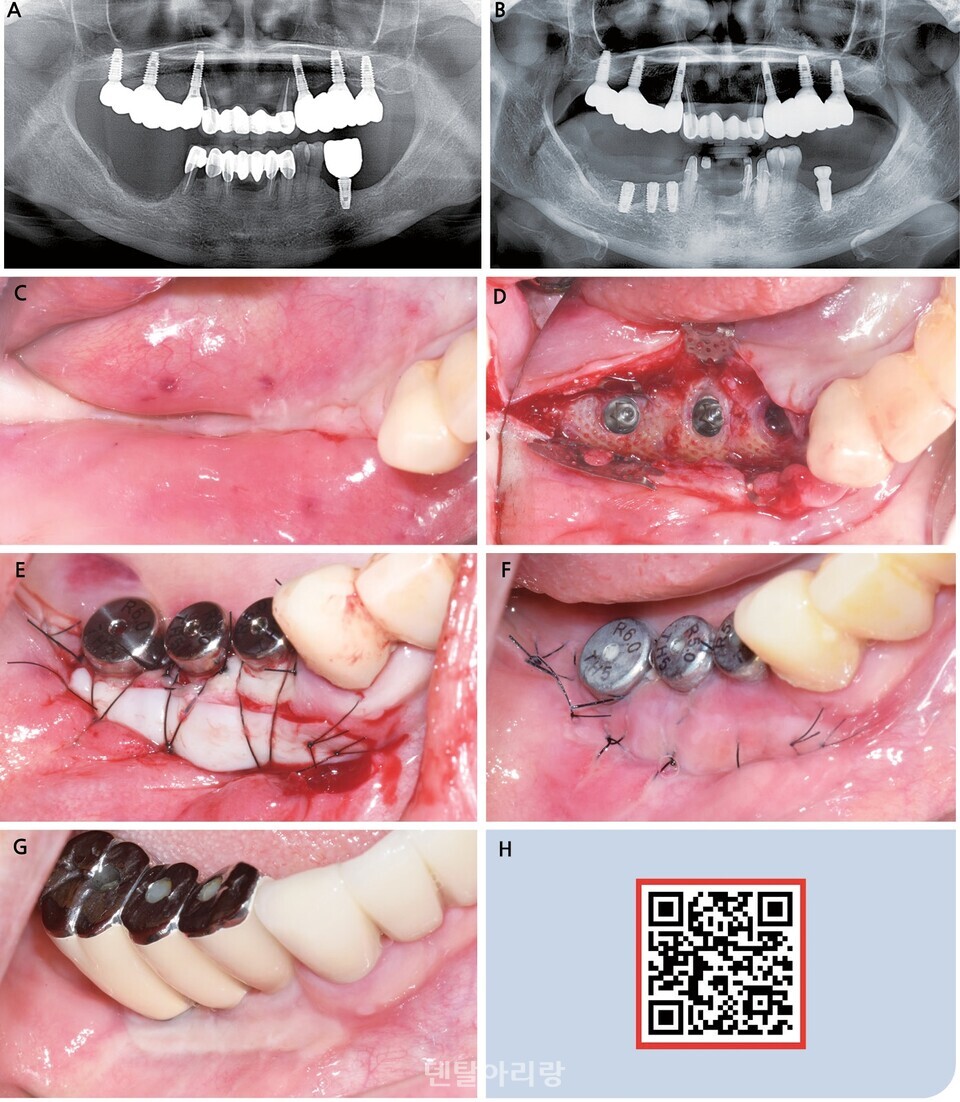

△ 그림 1. 이종 콜라겐 연조직 대체재 이식을 동반한 근단 변위 판막술을 통해 협측 구강 전정 깊이 및 협측 각화 점막 폭의 증대 증례. (a) 일차 수술 당시 골유도재생술을 동반 후 이차 수술을 앞두고 얕아진 협측 구강 전정 상태. (b) 협측 부분층 판막에 최소 1-2mm의 각화점막이 포함되도록 하여 판막을 형성 후, 수여부에 골막 천공을 시킨 위치에 맞춰 골막 봉합을 시행한 뒤, 치유지대주를 연결한 모습. (c) 이종 콜라겐 연조직 대체재의 모습. (d) 수여부 형태에 맞춰 연조직 대체재를 재단 후 골막 봉합으로 수여부에 고정한 모습. (e) 술 후 1주일 뒤 소독을 위해 내원 당시 치유 양상. (f) 술 후 2주일 뒤 봉합사 제거를 위해 내원 당시 치유 양상. (g) 보철물의 협측으로 충분한 깊이의 구강 전정과 비유동성 각화 점막이 형성된 모습.

아무리 수술이 단순해져도 지켜야 하는 원칙은 똑같다

자가 연조직 이식술 시 수여부를 적절히 형성하고 공여부로부터 떼어낸 이식편을 수여부에 단단히 고정하는 것이 치료의 성패를 좌우한다. 이러한 원칙들은 이종 콜라겐 연조직 대체재를 사용한다 하더라도 여전히 지켜져야 한다. FGG 대신 연조직 대체재를 사용하여 임플란트 주위 비유동성 각화 점막 폭을 증강시킴과 동시에 구강 전정의 깊이를 확보하고자 한다면, 수여부 형성 시 elastic fiber 층이 최대한 부분층 판막에 포함되도록 하여 수여부 표면에는 최대한 비유동성의 골막층만 남기는 것이 중요하고, 가능하다면 부분층 판막에 최소한 1-2mm의 각화점막을 포함되도록 하는 것이 치유에 유리하다. 또한 수여부에서 부분층 판막을 골막 봉합으로 고정할 위치에는 골막 천공 (periosteal fenestration)을 시켜 scar tissue band 생성을 유도함으로써, 근단 변위시킨 점막이 차후에 치관 방향으로 rebounding되는 현상을 예방하는 것이 예지성 있는 결과를 얻는 데에 도움을 주는데, 이는 전임상 동물실험과 후향적 임상연구를 통해 효과가 입증된 바 있다(그림 3). 그리고 연조직 대체재를 수여부에 적용할 때에는 치유 기간 중 움직이지 않도록 봉합 등의 방법으로 적절히 고정하는 것이 중요하다.